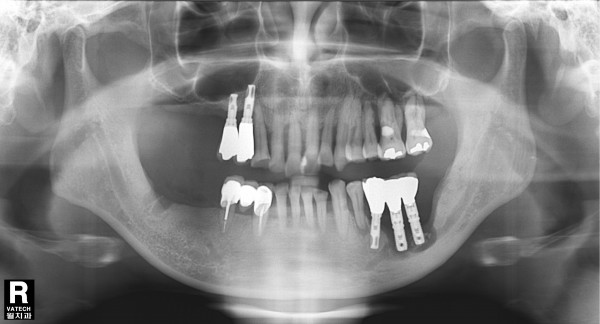

65세 남자 환자/ 하악 좌측 구치부 임플란트 제거 후 뼈이식 및 임플란트 재식립